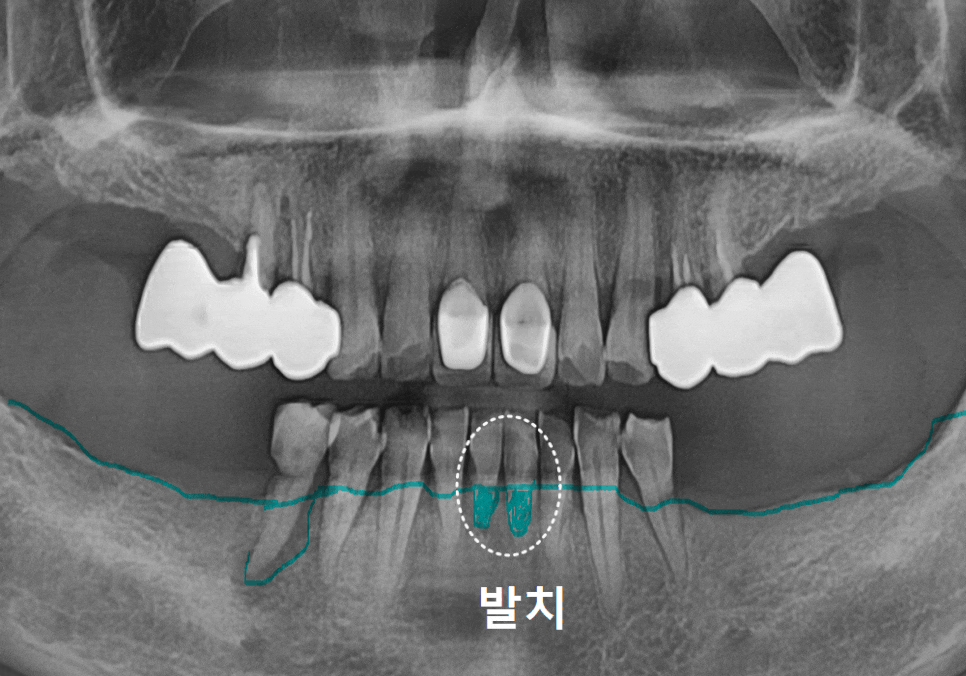

아래 앞니 부위는

어금니에 비해 폭이 좁고,

치아 뿌리 사이 간격도 촘촘해

임플란트를 여러 개 심을 공간이

부족한 경우가 있습니다.

이럴 때는

치아 2개를 발치했다고 해서

무조건 임플란트 2개를 심기보다,

공간과 교합 관계를 함께 고려해

임플란트 1개만 식립하고

좁은 공간을 자연스럽게

활용하는 방법도 가능합니다.

아래 앞니 2개 발치 후

임플란트 1개만 식립한 환자 사례

비용 부담을 크게 걱정하셨던 점

아래 앞니 부위의

잇몸뼈(치조골)가 비교적 얇았던 점